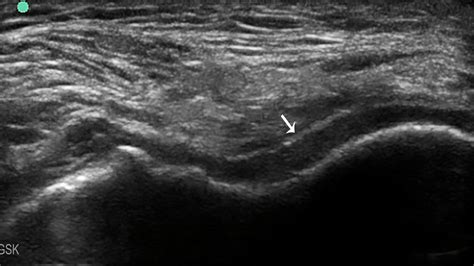

Ultrasound double contour sign. Transverse ultrasound image of the